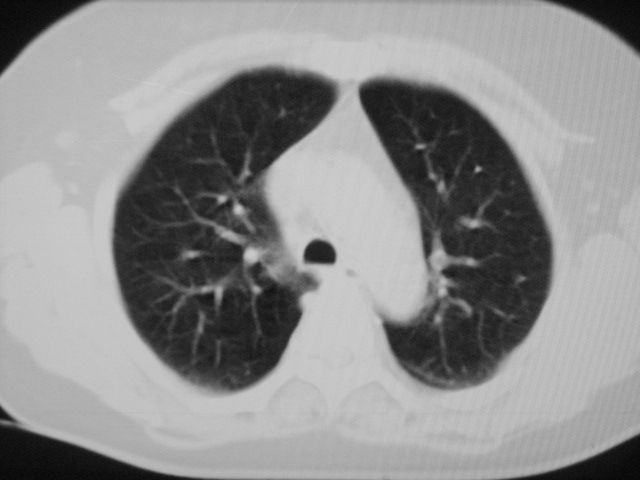

以下是引用清清楚楚在2007-8-28 7:13:00的发言:[br]右肺下叶可见斑片状高密度影,边缘模糊;右肺中叶内侧段及左肺舌段亦可见小斑片状模糊影。[br]考虑双肺感染,建议抗炎治疗后复查。

以下是引用天南地北在2007-8-27 23:49:00的发言:[br]右肺下叶可见斑片状高密度影,边缘模糊;右肺中叶内侧段及左肺舌段亦可见小斑片状模糊影。[br]考虑双肺感染,建议积极抗炎治疗后复查。

以下是引用天南地北在2007-8-27 23:49:00的发言:[br]右肺下叶可见斑片状高密度影,边缘模糊;右肺中叶内侧段及左肺舌段亦可见小斑片状模糊影。[br]考虑双肺感染,建议抗炎治疗后复查。

以下是引用难听在2007-8-28 13:17:00的发言:[br]右肺下叶背段支气管狭窄,是否可以考虑新生物伴阻塞性肺炎.请大家帮帮忙,这个病人是卫生局长的丈母娘.惹不起啊.